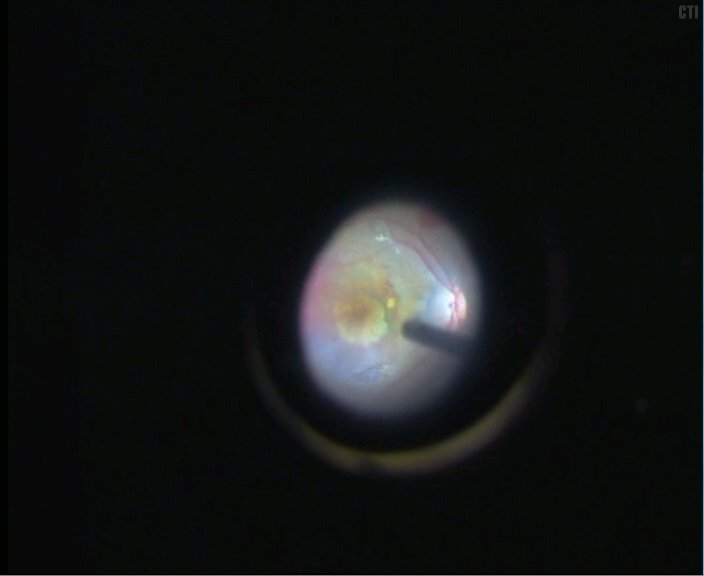

6、将色素上皮植片植入黄斑区下

7、手术结束后可见黄斑区下色素上皮移植片